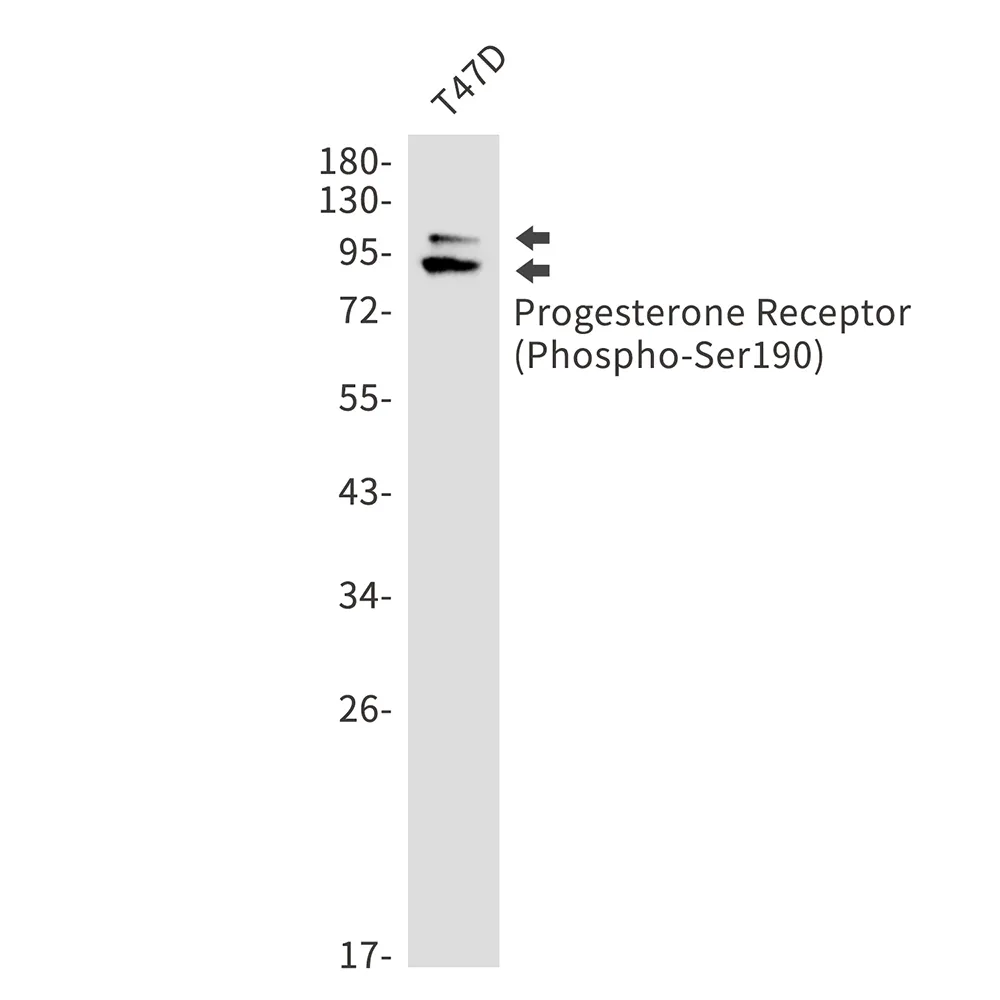

Phospho-Progesterone Receptor (Ser190) Rabbit Monoclonal Antibody

Cat: AMRe02476

Size1:50μl Price1:$188

Size2:100μl Price2:$338

Size3:500μl Price3:$1200

Size2:100μl Price2:$338

Size3:500μl Price3:$1200